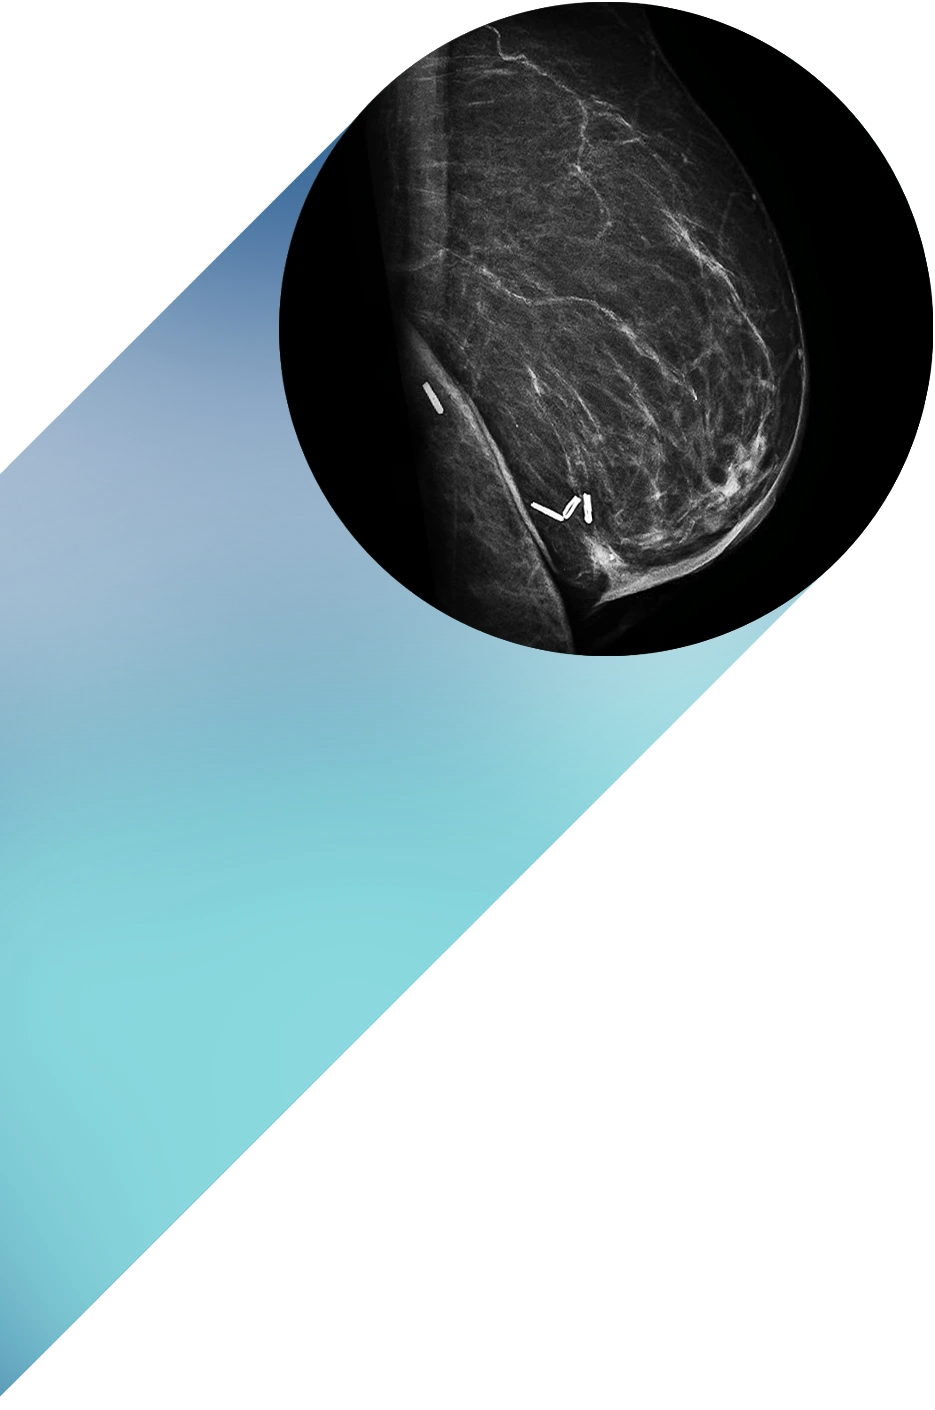

Nuestro compromiso ha sido, y sigue siendo, ofrecer estudios de máxima precisión con la tecnología más avanzada del país: Resonancia Magnética 3 Teslas con Inteligencia Artificial, Tomografía Multicorte de última generación, Radiografía digital, Mamografía digital y Ecografía de alta resolución.

Detecta cambios mínimos en el tejido mamario con imágenes de máxima nitidez y en pocos segundos, gracias a equipos digitales de última generación que priorizan tu comodidad y seguridad.